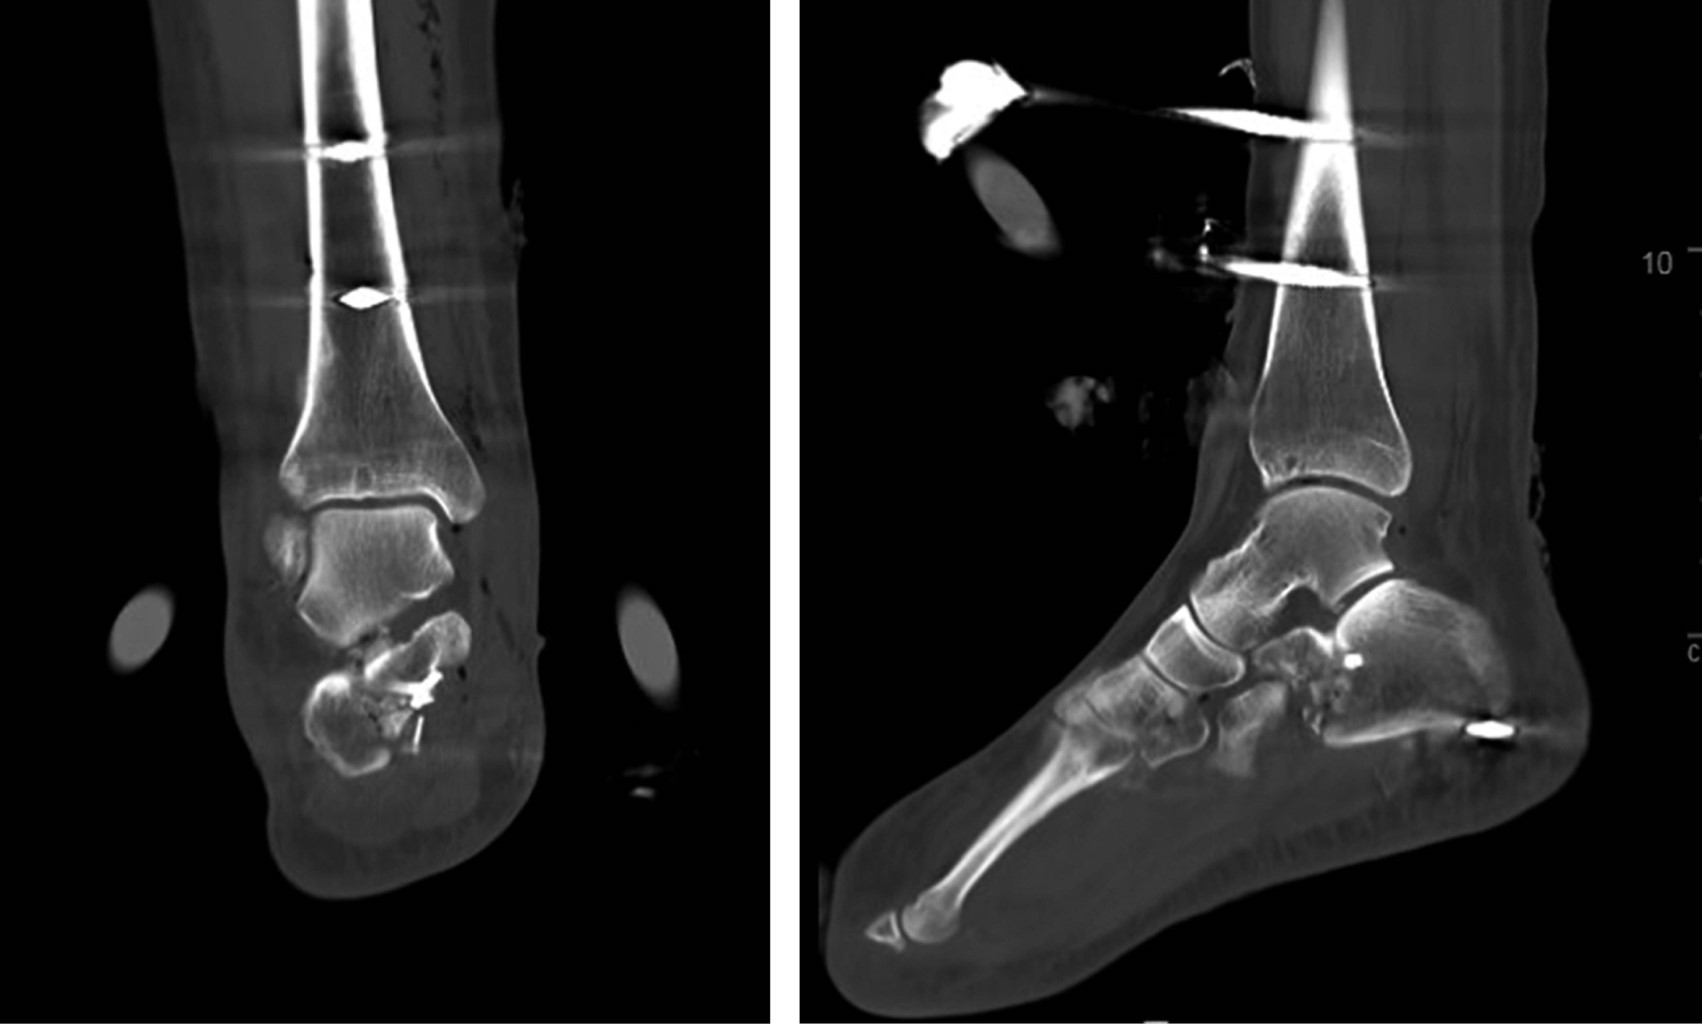

Introduction: subtalar dislocations, typical of high-energy trauma, are classified as medial, lateral, anterior or posterior depending on the deviation of the foot in relation to the talus. Lateral dislocation accounts for 17% of the total and has a worse prognosis. Immediate reduction is required to reduce the risk of sequelae, the incidence of which is around 90%. Objective: a case of lateral subtalar dislocation is presented; a review of the literature on its diagnosis, treatment and prognosis is carried out. Clinical case: a 46-year-old woman fell from a height of 3 meters, with severe deformity in the hindfoot. There was good distal vascular coloration, but no pulse or posterior tibial sensitivity could be identified. In addition, she had a medial sulcocutaneous fold under the head of the talus. Plain radiograph and CT revealed lateral subtalar dislocation, with fracture of the sustentaculum tali, and a "fleck sign" in the posterior region of the distal fibula. Suspecting soft tissue incarceration, a medial approach was performed, observing interposition of the posterior tibial neurovascular bundle. After joint reduction, the sustentaculum tali and the "fleck sign" were osteosynthesized. In addition, a complete section of the long lateral peroneal tendon was identified, which was tenodesed to the short peroneal tendon. Finally, an external fixator was placed. After eight weeks, the fixator was removed and weight bearing was authorized; after six months, mobility was complete and hypoesthesia persisted only in the plantar pad. Conclusions: lateral subtalar dislocation is an uncommon entity with a poor prognosis. Adequate interpretation through a thorough examination and pre-reduction CT of the bone and soft tissue lesions minimizes future sequelae.

Figure 4

Figure 5